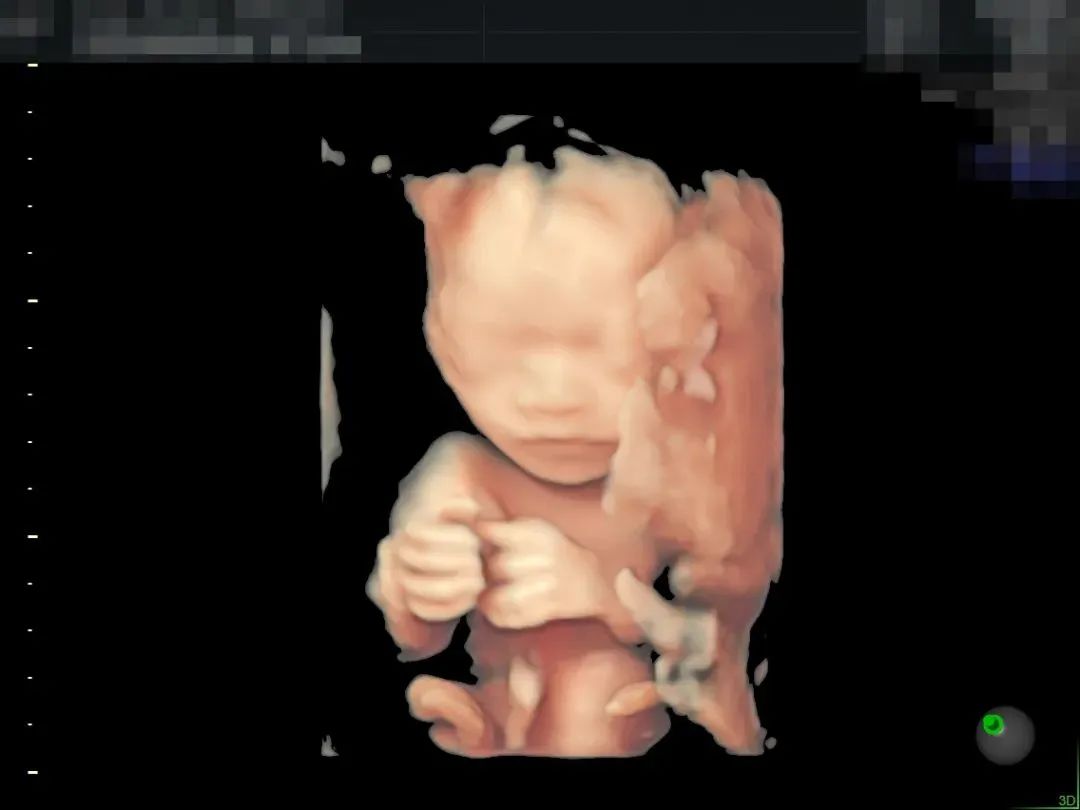

▲190斤孕妈王女士,不仅做了全面筛查,还留下了宝贵的胎儿影像,全家人都非常满意

超高清画质立体显示胎儿面部、脏器、四肢脊柱等发育情况,可高效筛查胎儿唇裂、骨骼发育异常以及中枢神经系统、呼吸系统、消化系统、泌尿系统、心脏的重大畸形。金标E10具备一整套胎心成像技术,支持从胎儿心脏结构到心功能的分析,可真实呈现胎心结构、脐带、血流变化,帮助临床医生及时作出诊断。“金标版”E10超真动态显示胎儿实时活动图像,画质全面颠覆传统视觉理念,堪比IMAX电影大片,让您看得更清晰、更直观。“金标版”GE-E10四维彩超,采用人体工程学设计,不存在射线、光波和电磁波等方面的辐射,对人体健康没有影响,孕妈妈们也可以安心检查。